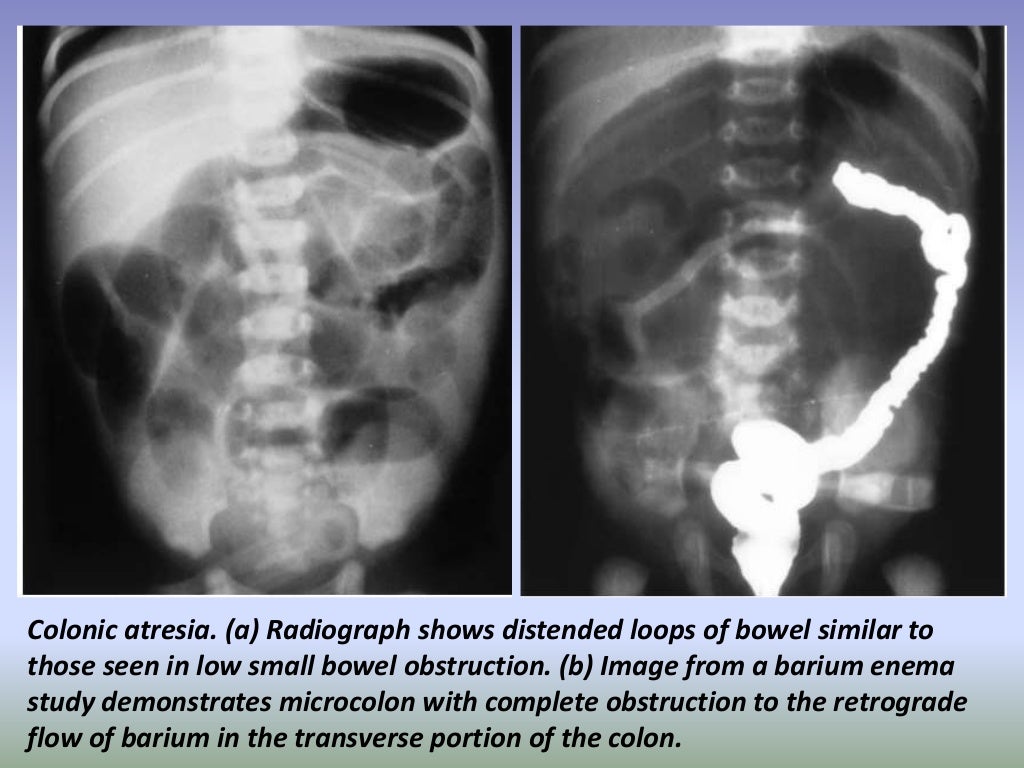

Presentation1.pptx, radiological imaging of large bowel diseases Large Bowel Disease Diagnosis inflammatory bowel disease (ibd) encompasses two conditions: inflammatory bowel disease is a term that refers to crohn’s disease and ulcerative colitis, two inflammatory conditions that affect as. Crohn’s disease and ulcerative colitis. inflammatory bowel disease (ibd) refers to diseases that cause chronic inflammation in your gastrointestinal (gi). chronic diarrhea and belly pain could be caused by. Large Bowel Disease Diagnosis.